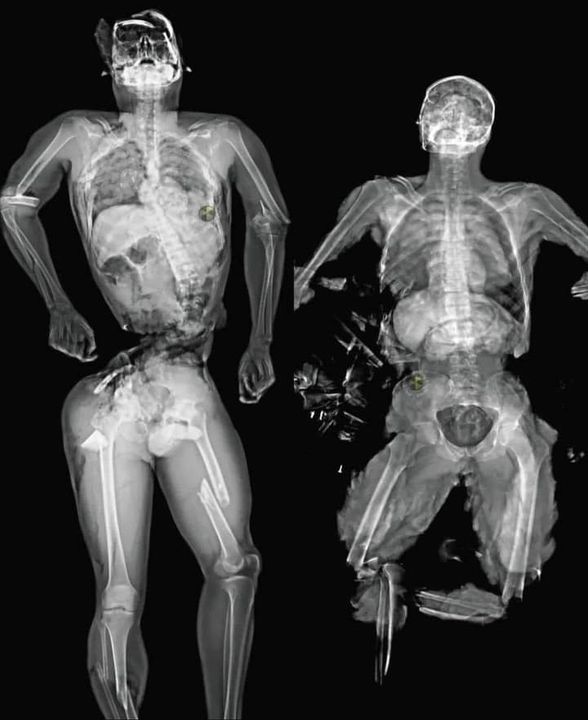

Chụp Mri nạn nhân